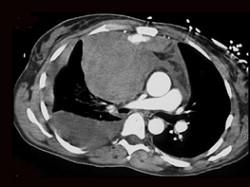

男,33岁,右胸部外伤,胸闷、气短,结合CT图像,最可能的诊断是 ( )A、淋巴管瘤B、淋巴瘤C、纵隔血肿D、畸胎瘤E、胸腺瘤

问题 男,33岁,右胸部外伤,胸闷、气短,结合CT图像,最可能的诊断是 ( )

选项 A、淋巴管瘤 B、淋巴瘤 C、纵隔血肿 D、畸胎瘤 E、胸腺瘤

答案 C